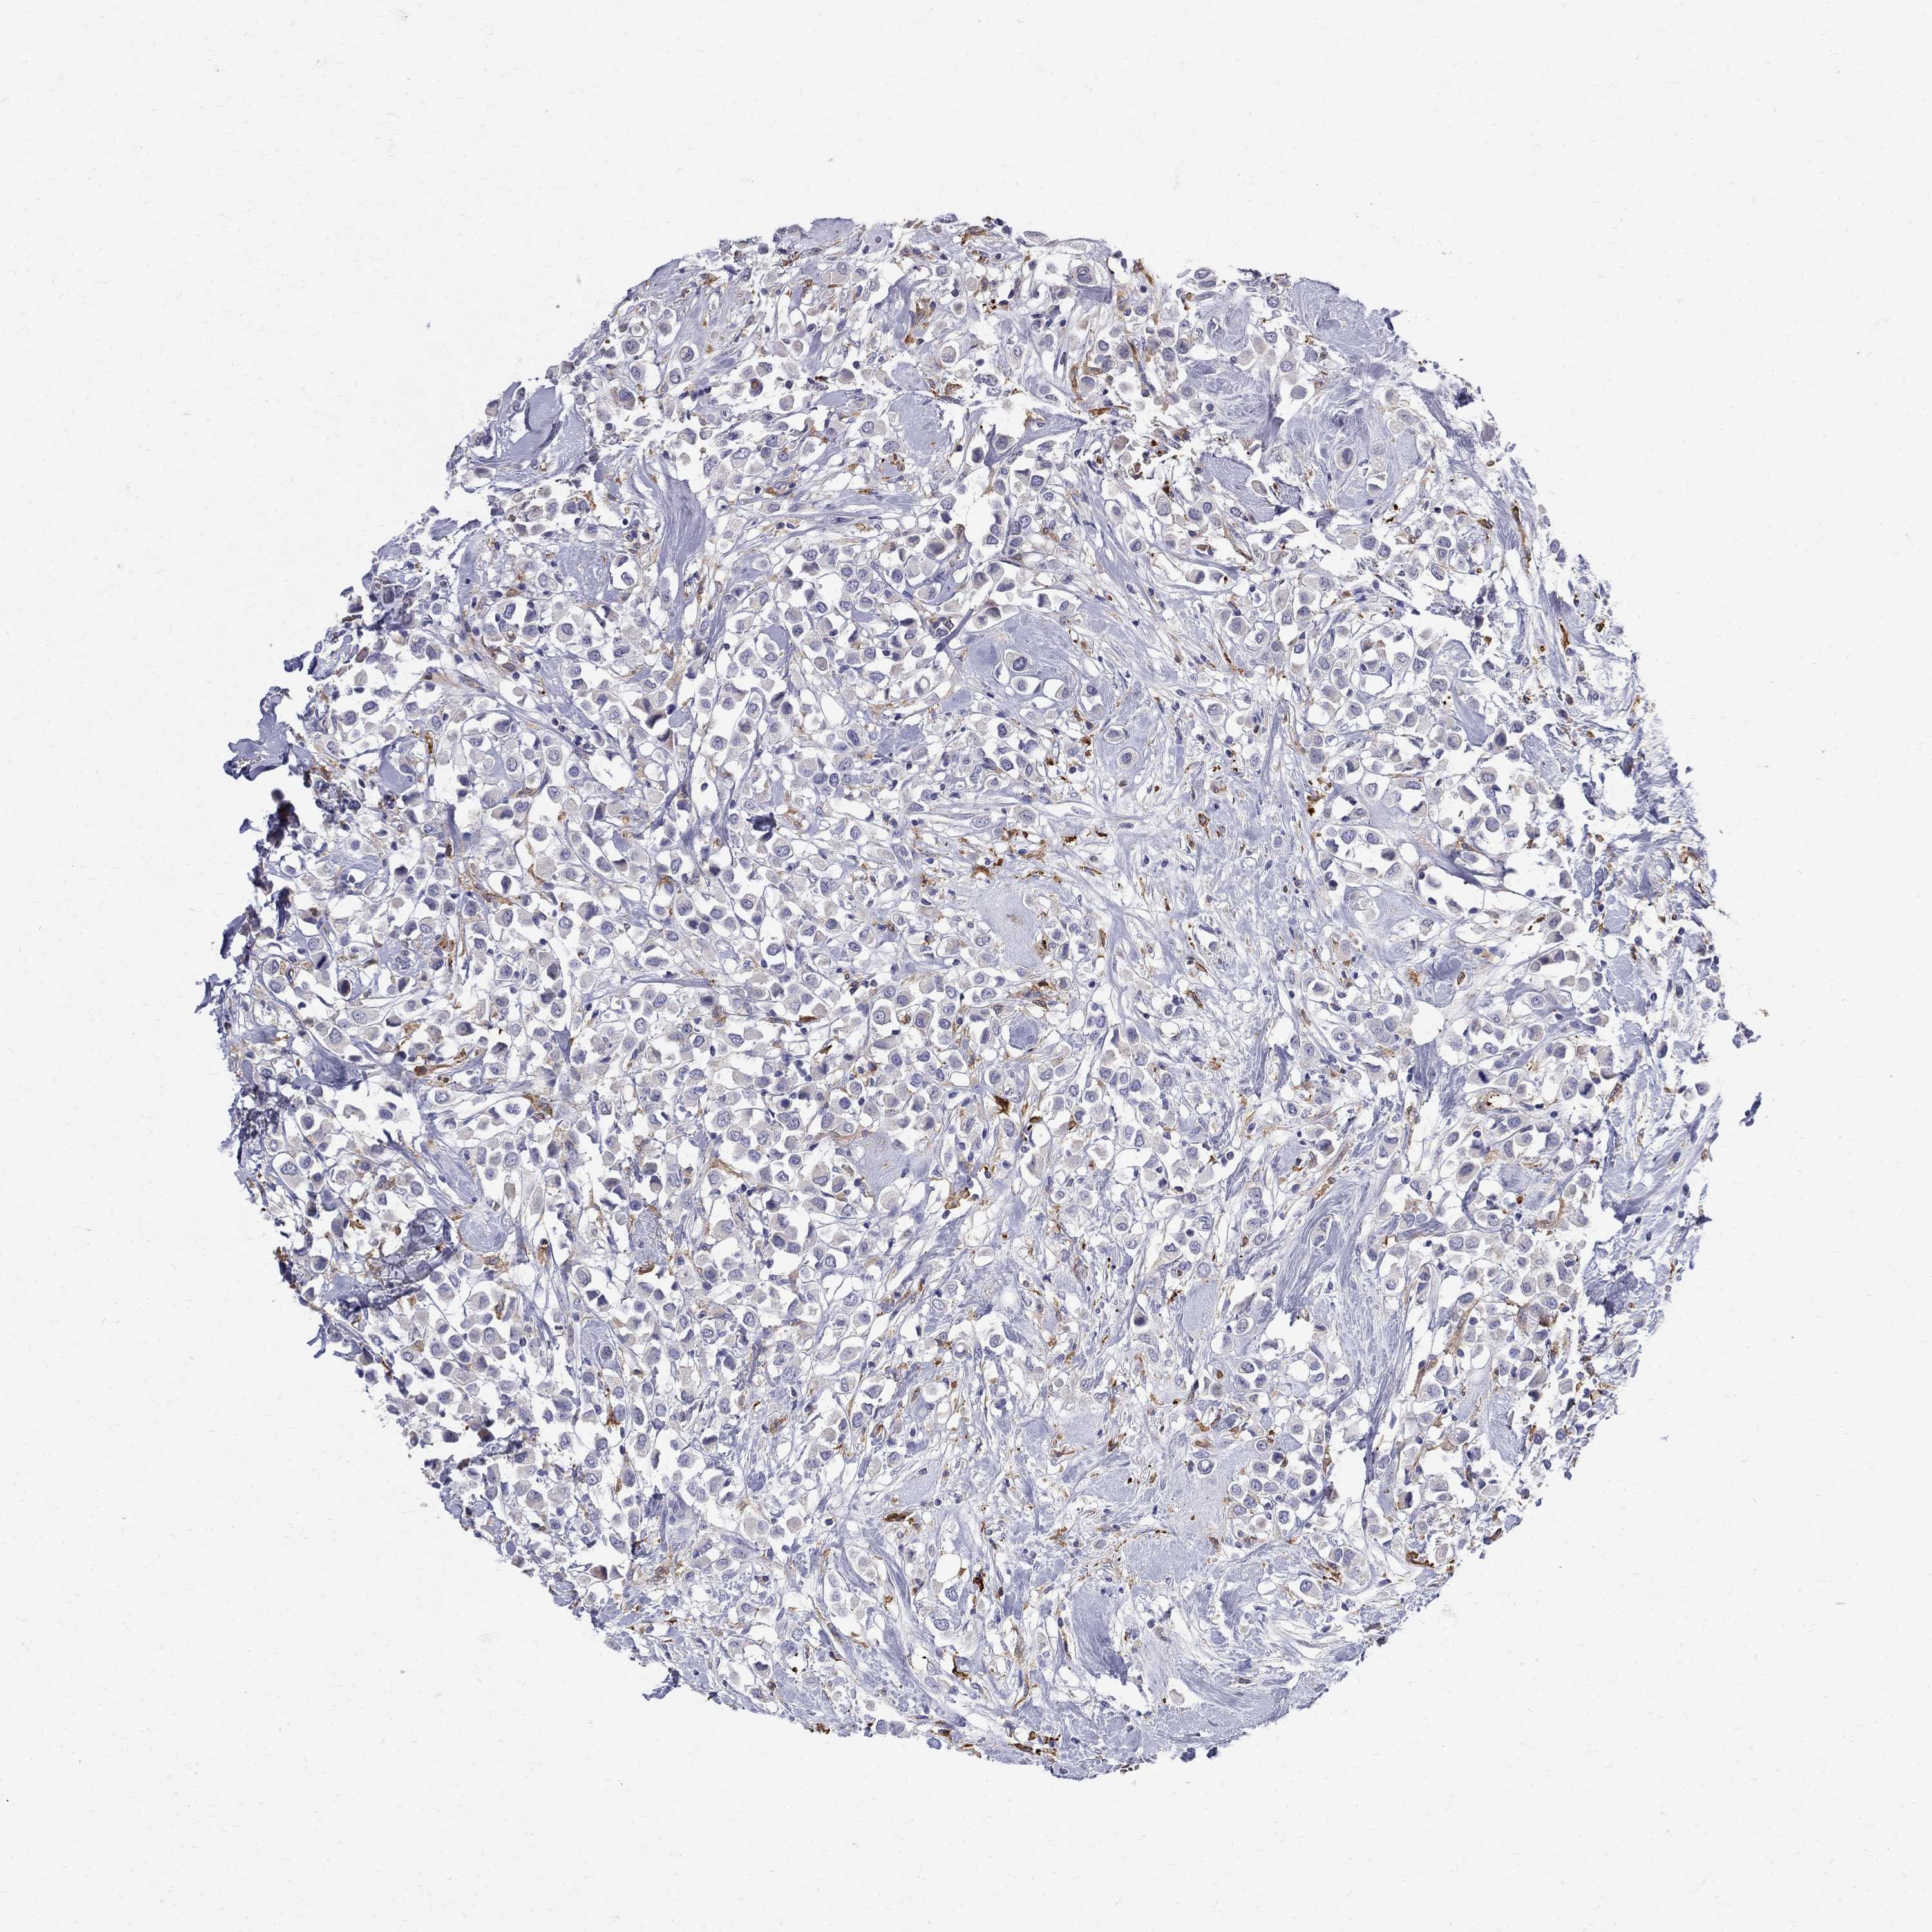

CANCER BREAST CANCER Show tissue menu

BRCA TCGA BRCA VALIDATION PROTEIN EXPRESSION

Breast cancer

Human cancer

AGER is not prognostic in Breast Invasive Carcinoma (TCGA)